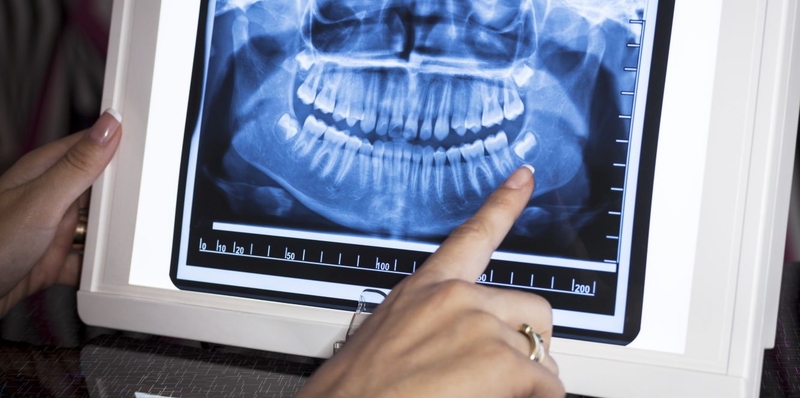

Máy chụp X quang răng sử dụng trong nha khoa

Máy chụp X-quang răng sử dụng trong nha khoa